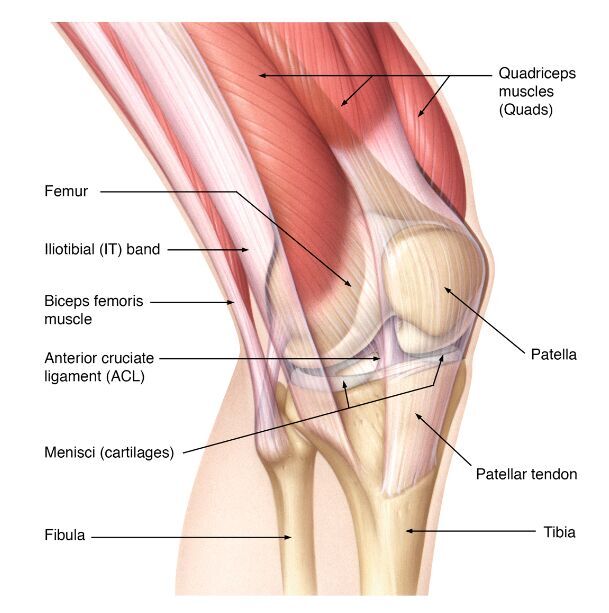

Name A-D

A

A- Lateral collateral ligament

B- Anterior cruciate ligament

C- Posterior cruciate ligament

D- Medial collateral ligament

16

Q

Name A-H

A- iliotibial band

C- Menisci

D- Fibula

E- Quadricep muscles

F- Patella

G- Patellar ligament

H- Tibia